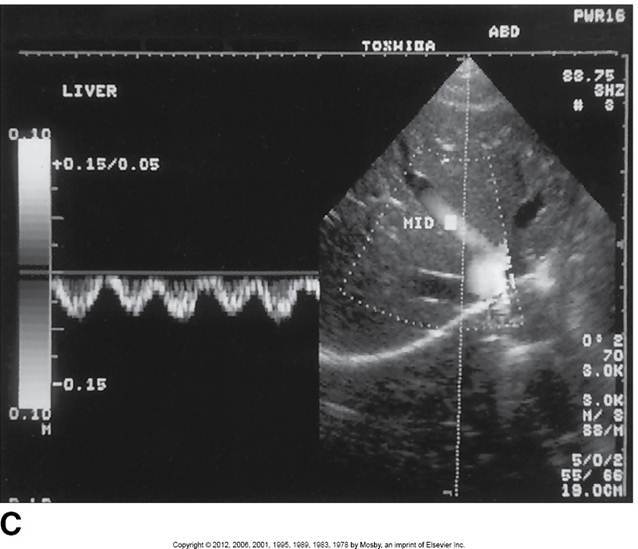

Middle Hepatic vein